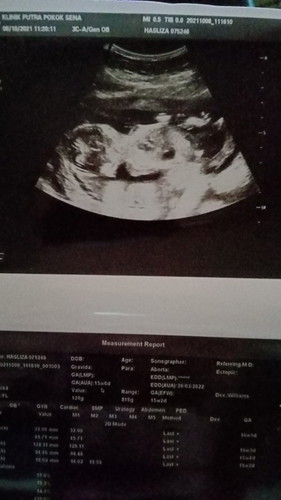

Umur sis dh 45 tahun..sekarang hamil 18 minggu.. Alhamdulillah.baik2 ja sis..cma sis nk kepastian ..siapa blh terangkan x..sis akan dpt bby pa ya.. sis kurang fhm tgk pada gambar scan.. hri tu terlupa nk tyn doktor. Dan doktr pn x ckp pa 😅

Ikut gmbr scan ni tak nampak gender puan. Ni gambar overall satu badan dgn kepala. Nak tgk gender kena gmbr yg nampak celah kangkang. Masa scan tu ada minta nk tgk gender tk? Kalau tk minta kadang diorang tk scan utk tunjuk.